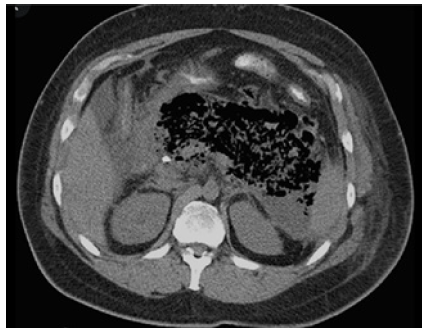

Infection of collections - 33% of patients with necrotizing pancreatitis (Figure 2).